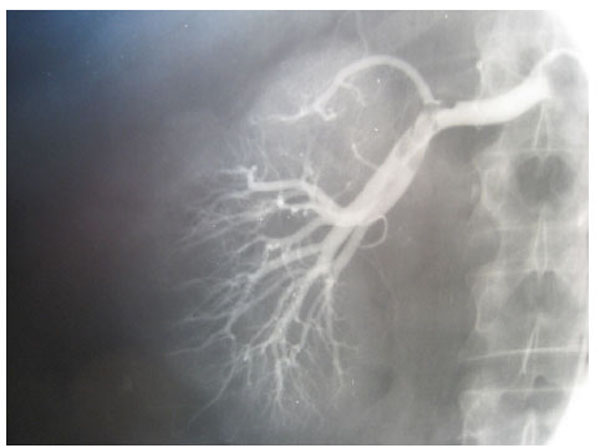

Fig. (3), Fig. (4), Fig. (5), Fig. (6), show images before and after systemic fibrinolytic treatment of two different patients, one suffering from partial emboli occlusion of main renal artery and the other, multiple segmentary intrarenal emboli.

Fig. (5).

Left selective renal arteriography showing multiple segmentary intrarenal emboli.